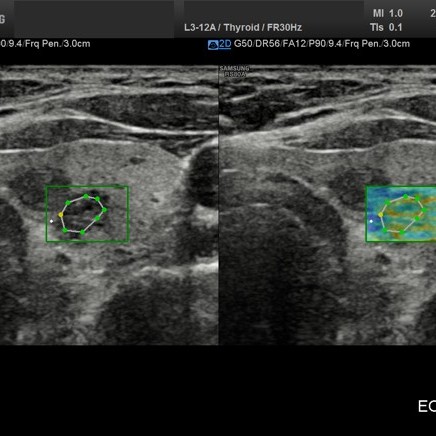

• USG tarczycy

z oceną węzłów, możliwością oceny zmian w elastografii oraz przy użyciu biopsji.

Elastografia.

To przełomowa metoda diagnostyczna wykorzystującą fakt, że chora tkanka zmienia swoją twardość. Można powiedzieć, że elastografia jest cyfrowym rozwinięciem badania dotykiem, kiedy lekarz ocenia twardość i spoistość badanego narządu.

Elastografię proponujemy przede wszystkim w przypadkach:

• podejrzanych zmian w tarczycy

W wielu przypadkach elastografia pozwala uniknąć biopsji i rozwiać wątpliwości co do łagodnego, lub złośliwego charakteru zmiany.

Badanie elastograficzne można wykonać w naszej pracowni jako rozszerzenie badania USG tarczycy i piersi (ocena guzków), a także jako samodzielne badanie – elastografia wątroby w celu oceny włóknienia(stosowana u nas metoda elastrografii 2D-SWE jest znacznie dokładniejsza od dotychczas stosowanej metody TE [FIBROSCAN®].